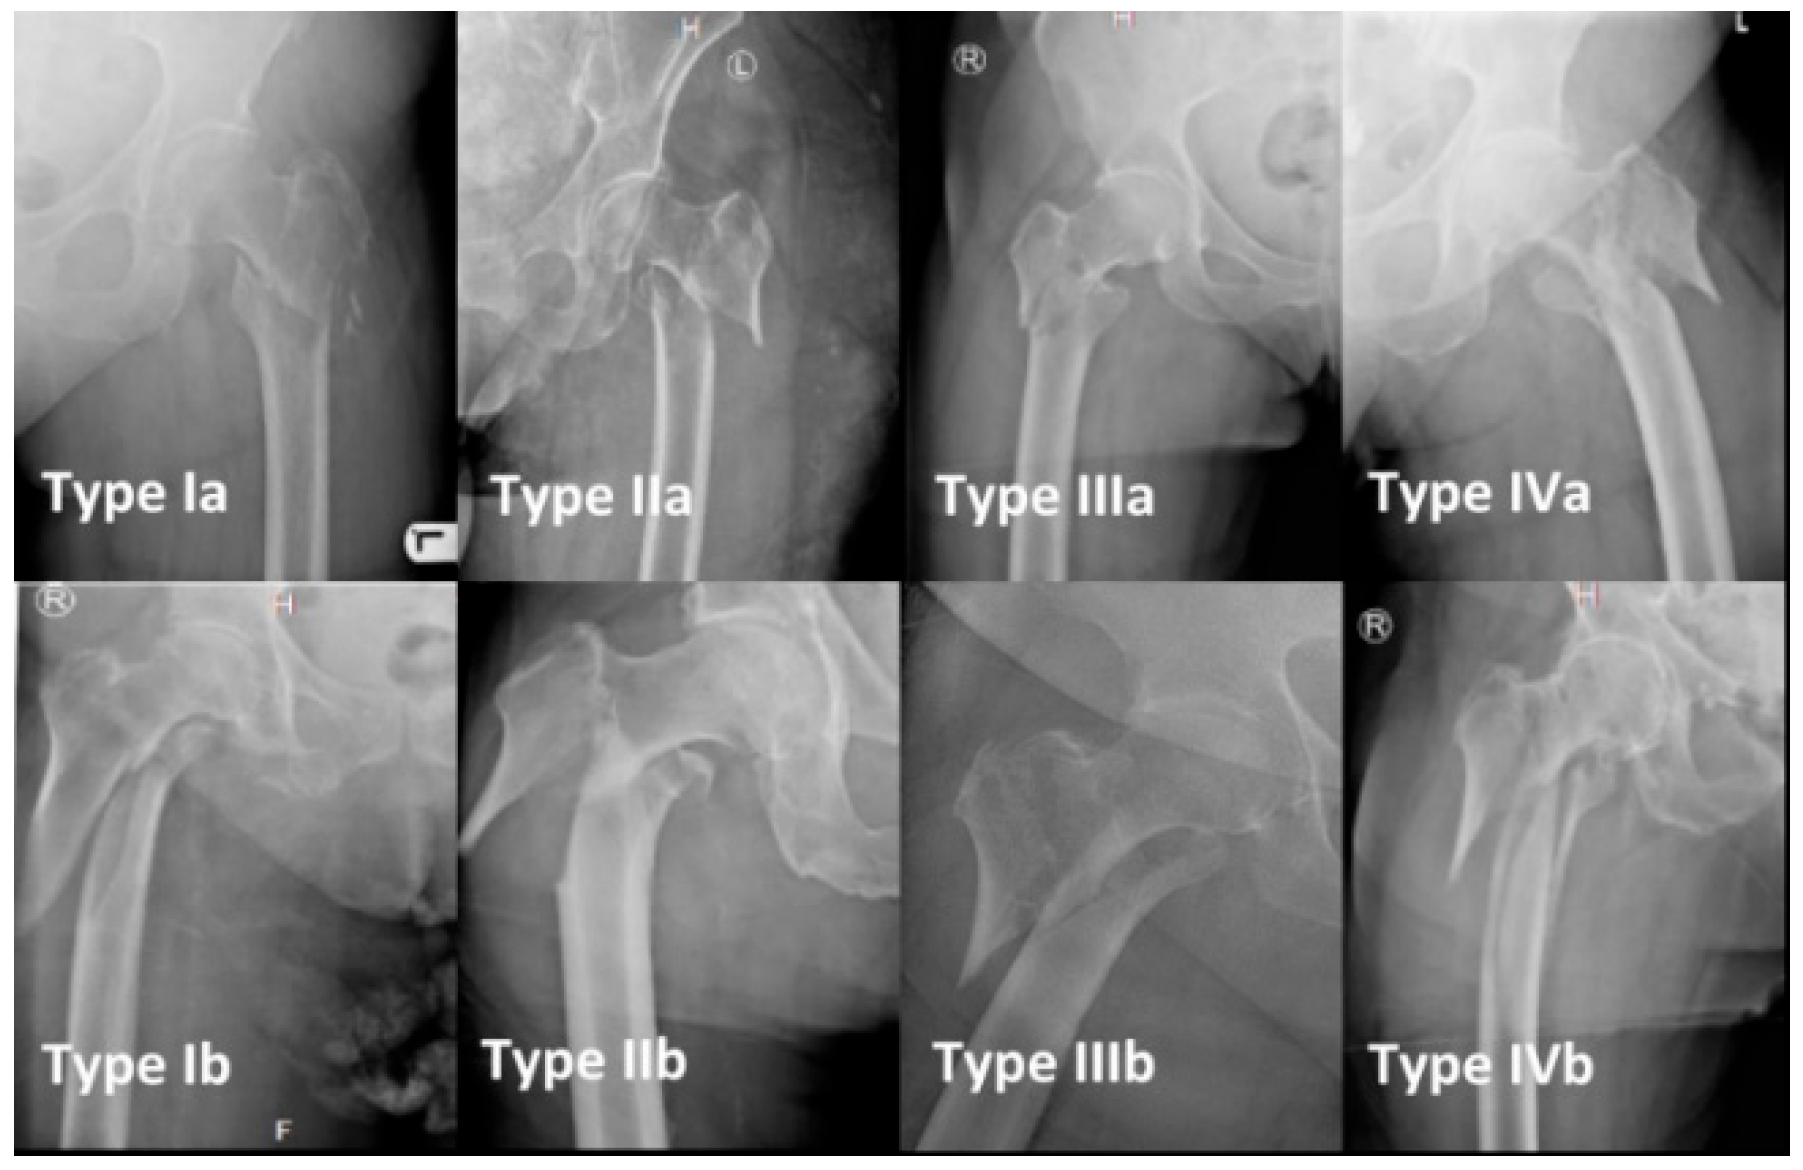

3.1. Classification

- Breuer, R.; Lang, N.; Zeitler, C.; Fiala, R.; Kasparek, M.F.; Widhalm, H.K. Surgical treatment of reversed oblique trochanteric femur fractures: Clinical outcome and introduction of a novel surgical classification. Injury 2025, 56, 112725. [Google Scholar] [CrossRef]